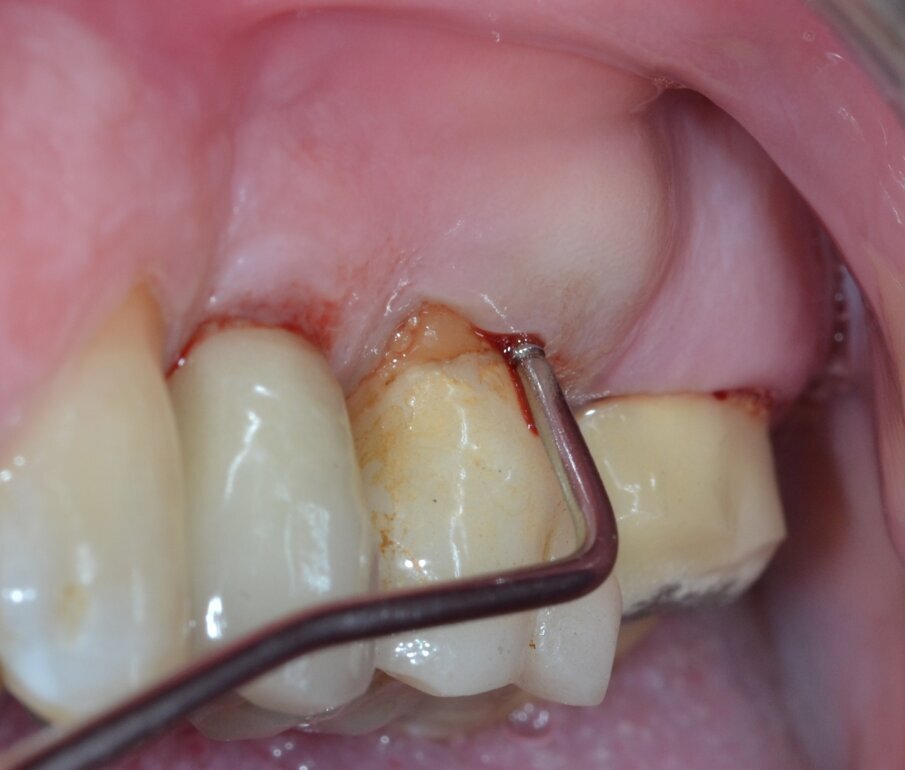

Paziente di aa 56, maschio, giunge alla nostra osservazione lamentando dolorabilità alla palpazione e alla masticazione in corrispondenza dell’elemento 1.6 sottoposto a terapia endodontica diversi anni prima. All’esame obiettivo si rileva la presenza di un’ampia raccolta ascessuale vestibolare associata a una profonda lesione parodontale nella zona della forcazione radicolare buccale (Fig. 1). Il sondaggio nel resto del cavo orale non evidenzia la presenza di altre lesioni parodontali (Fig. 2) mentre l’indagine radiografica rivela la presenza di un’ampia area di radiotrasparenza che coinvolge tutto lo spazio periapicale a partenza dalla radice mesio-buccale (Fig. 3). Sulla base dei dati clinici e radiografici acquisiti viene pertanto confermata la diagnosi di lesione endo-parodontale; nello specifico, si tratta di una lesione endodontica primaria con secondario interessamento parodontale e coinvolgimento della forcazione radicolare di Classe 3 secondo Hamp & Nyman3.

Fig. 2 - Sondaggio parodontale preoperatorio.